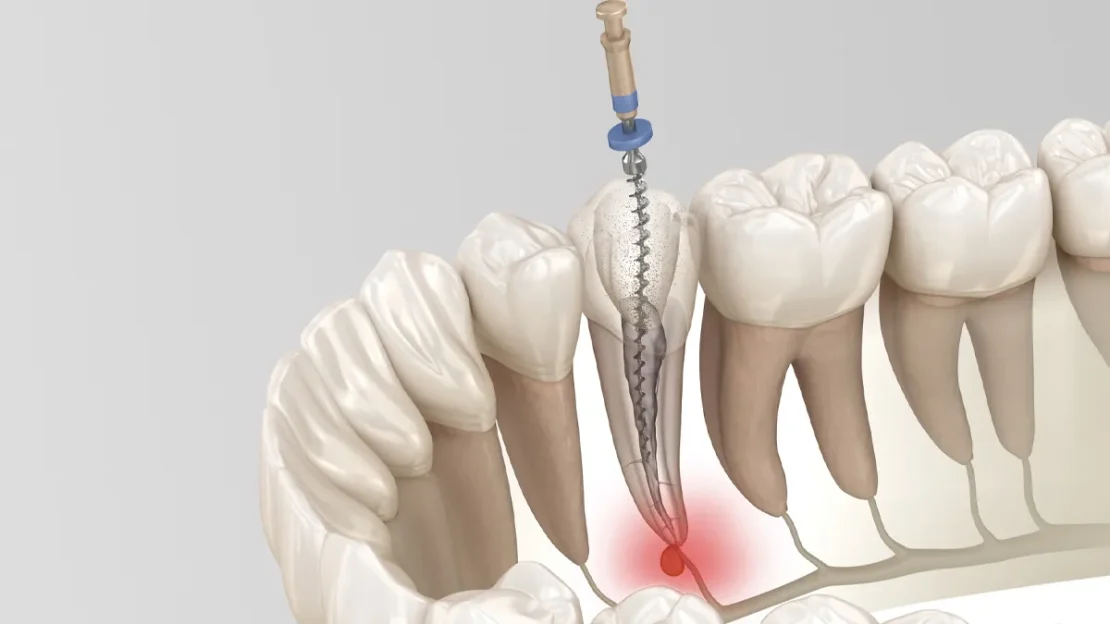

عکس پروتز کامل دندان مصنوعی

پروتز کامل دندان چیست؟ (پاسخ به سوالات رایج درباره آن)

از دست دادن تمام دندان‌ها، نه‌تنها جویدن غذا، بلکه کیفیت زندگی، اعتمادبه‌نفس و فعالیت‌های روزانه‌ی فرد را با چالش‌هایی روبه‌رو می‌کند. ...